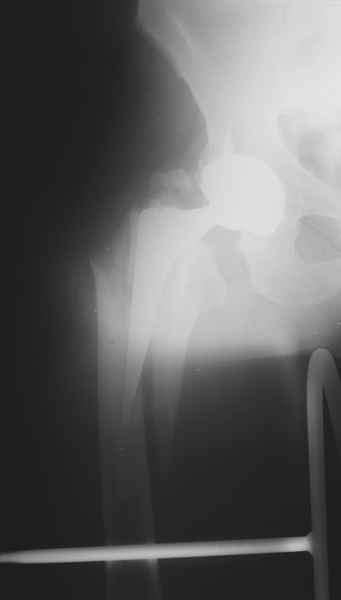

2. Применение ножки дистальной фиксации, мы отдаем предпочтение ножке Вагнера с фиксацией проксимального отдела на ножке. Более травматичное вмешательство, но при стабильной фиксации ножки реабилитация идет в обычном режиме.

Хочется показать два подобных случая, П-ка З. 72 лет и п-т Г. 80 лет. Сразу принимаю замечание, что это были ножки цементной фиксации, просто под руками не было бесцементника.

С уважением, Р.Тихилов